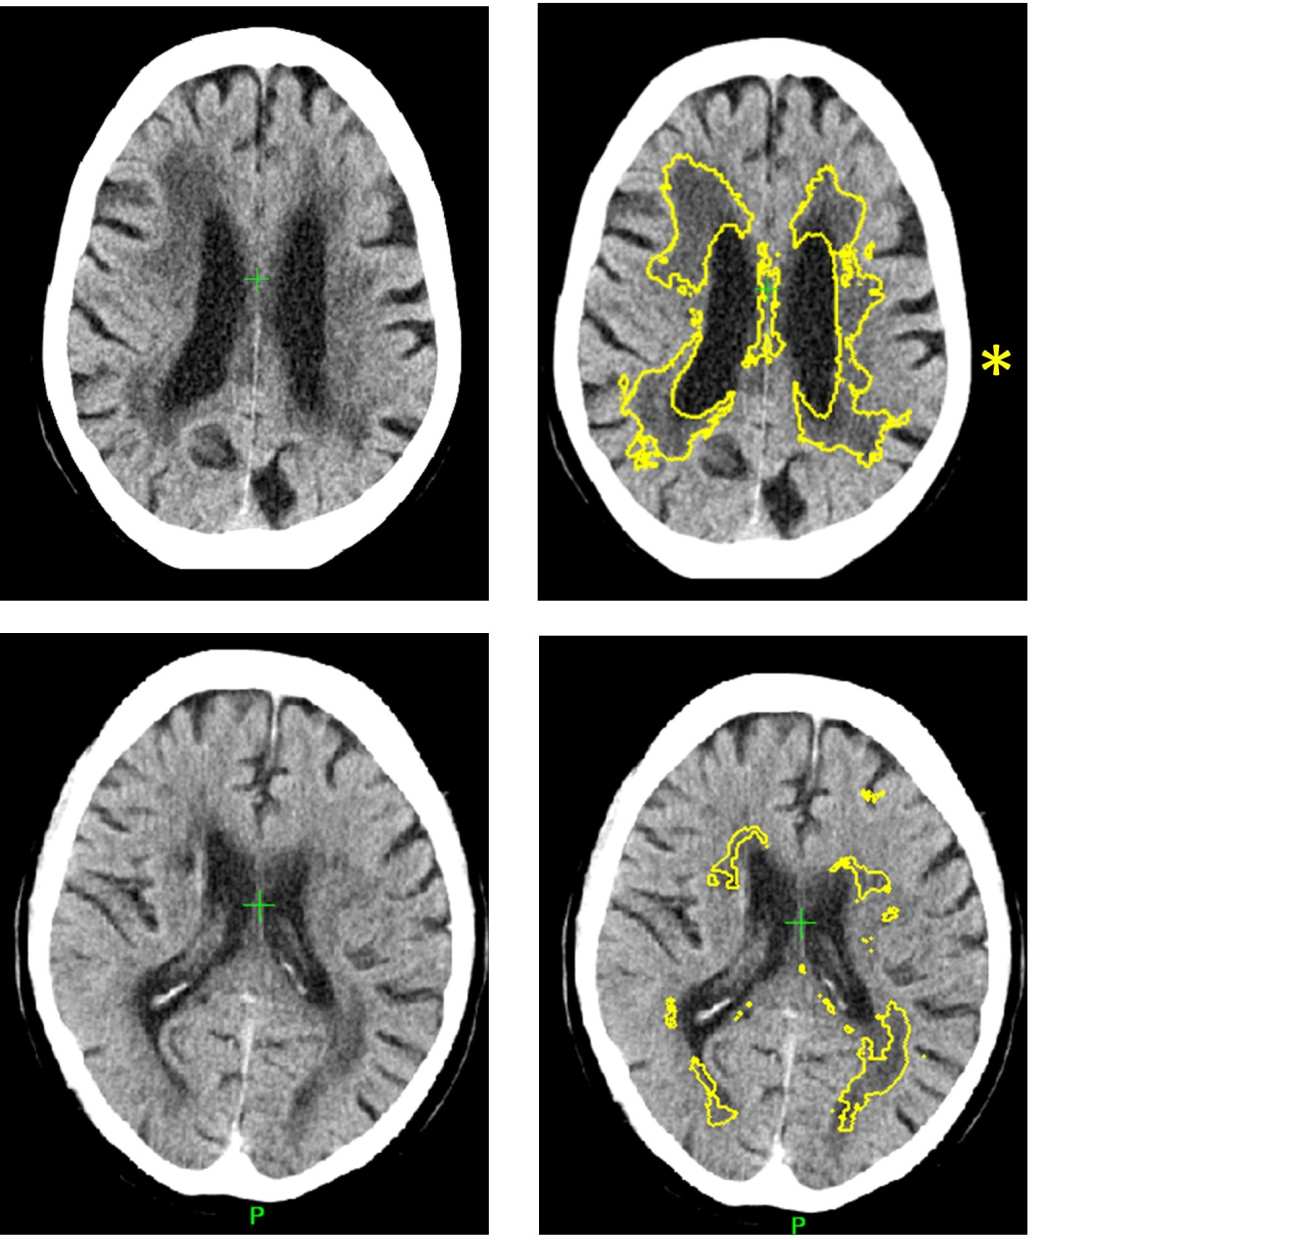

At the moment, doctors diagnose SVD by looking for changes to white matter in the brain during MRI or CT scans. However, this relies on a doctor gauging from the scan how far the disease has spread. In CT scans it is often difficult to decide where the edges of the SVD are, making it difficult to estimate the severity of the disease, explains Dr Bentley.

Dr Bentley added: “Current methods to diagnose the disease through CT or MRI scans can be effective, but it can be difficult for doctors to diagnose the severity of the disease by the human eye. The importance of our new method is that it allows for precise and automated measurement of the disease. This also has applications for widespread diagnosis and monitoring of dementia, as well as for emergency decision-making in stroke.”

The study used historical data of 1082 CT scans of stroke patients across 70 hospitals in the UK between 2000-2014, including cases from the Third International Stroke Trial. The software identified and measured a marker of SVD, and then gave a score indicating how severe the disease was ranging from mild to severe. The researchers then compared the results to a panel of expert doctors who estimated SVD severity from the same scans. The level of agreement of the software with the experts was as good as agreements between one expert with another.

Additionally, in 60 cases they obtained MRI and CT in the same subjects, and used the MRI to estimate the exact amount of SVD. This showed that the software is 85 per cent accurate at predicting how severe SVD is.